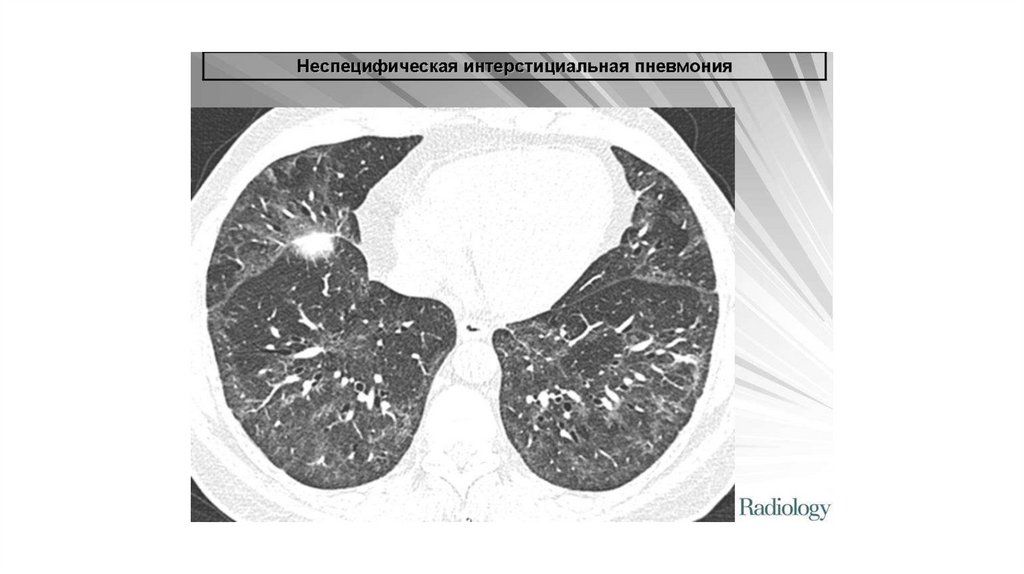

При рентгенографии грудной клетки при НСИП чаще всего

выявляются двусторонние изменения по типу «матового

стекла» и ретикулярные изменения в нижних отделах лёгких.

Характерным признаком НСИП при компьютерной томографии

высокого разрешения является симптом «матового стекла»,

часто в сочетании с признаками лёгочного фиброза

(уменьшение объёма лёгких, ретикулярные изменения,

тракционные бронхоэктазы). Типичная картина КТВР при НСИП

включает смешанный паттерн «матового стекла» и

консолидации (в случае выраженного клеточного

воспаления), а также иррегулярные линии с типичным

периферическим, субплевральным, базальным

симметричным распространением (при фибротическом

варианте).